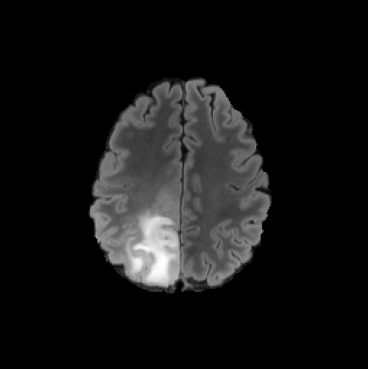

While ACAT revolves around generating counterfactuals, its primary strength lies in accurately identifying pathological regions, which are subsequently employed in a classification pipeline. On the other hand, it falls short in producing credible counterfactual examples, an issue we aim to address in this study. An illustration of this phenomenon is depicted in Figure 2, where we can observe how ACAT is able to generate a saliency map that approximately identifies the pathological region (e, bottom row). However, in the counterfactual example, the lesion remains visible (e, top row). In contrast, our approach not only refines the saliency map but also generates a counterfactual image where the pathology is completely eliminated (f).

4.3 Counterfactual Examples

In Figures 2 and 4 we display examples of healthy images and anomaly maps obtained with the different approaches. We can observe that f-Ano GAN is not able to generate credible counterfactuals and generally produces images of poor quality and unrealistic appearance. On the other hand, the approaches based on diffusion models are able to create more high-quality results. However, the ones obtained with CG and CFG seem to present some artifacts, which may not only impact the realism of the counterfactual examples but also the precision of the anomaly maps obtained from them. In order to better quantify the capability of these methods to accurately segment pathological areas, we compute the Dice scores of the anomaly maps they generate.